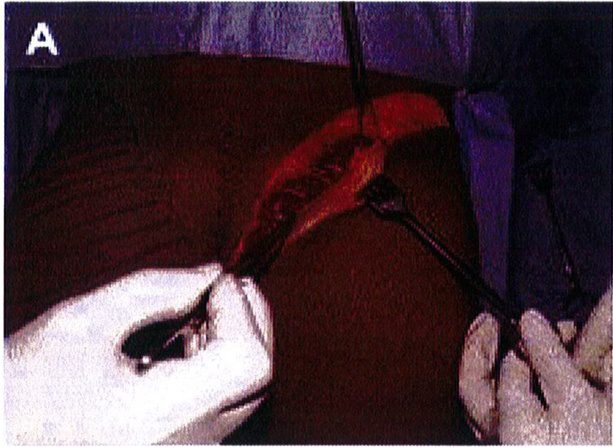

Hình. 3. (A) Lớp cân mạc che phủ cơ mông lớn. (B) Bóc tách lớp cân và cơ để tạo mặt phẳng cấy ghép. (Trích từ de la Pena JA, Rubio OV, Cano JP, et al. Subfascial Nâng mông. Clin Plast Surg 2006;33:409; đã xin phép trước khi đăng tải.)

Hình. 9. Đánh dấu các mốc giải phẫu quan trọng. (A) Đường rạch cân cơ mông lớn bắt đầu từ bờ ngoài xương cùng (B) Bắt đầu bóc tách lớp cân từ đường rạch ban đầu (Trích từ de la Pena JA, Rubio OV, Cano JP, et al. Subfascial Gluteal aug- mentation. Clin Plast Surg 2006;33:411; đã xin phép trước khi đăng tải.)